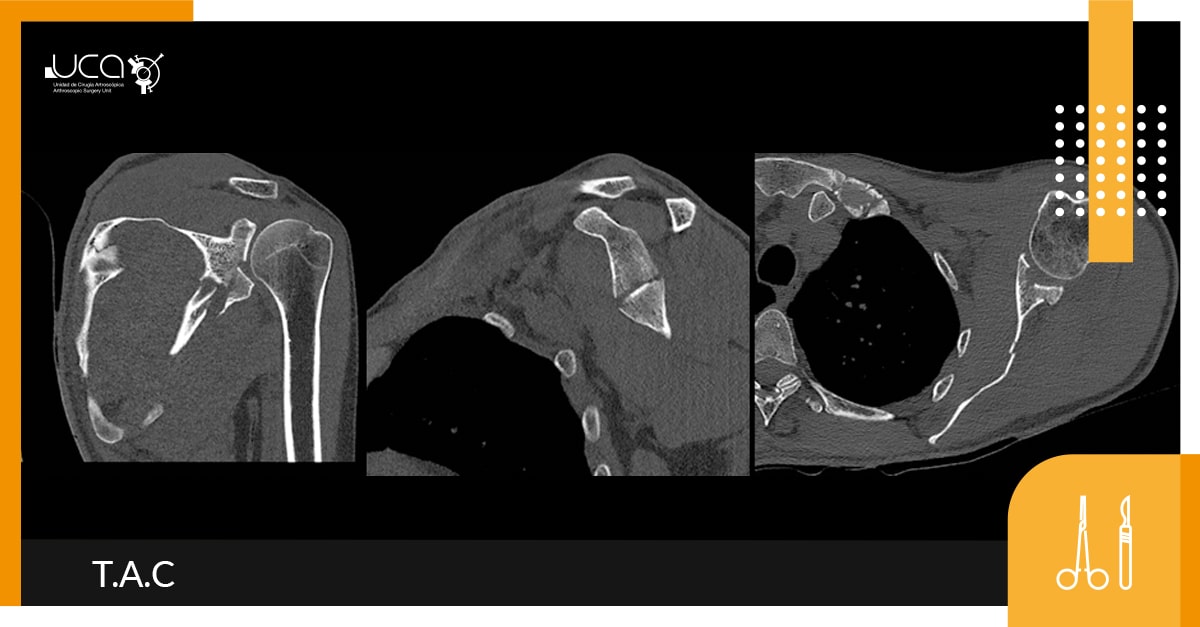

El T.A.C. nos muestra una fractura compleja de escápula que presenta un trazo en el cuerpo que se extiende al cuerpo y en el aspecto marginal a la glenoides. El trazo del cuello es oblicuo de inferior a superior desde el margen escapular lateral superior al borde medial y afectando a la espina de la escápula.

La afectación glenoides afecta a la glenoides inferior, es intraarticular, con un trazo completo. El fragmento glenoideo posterior e inferior esta desplazado de forma inferior, mide 18x24mm.